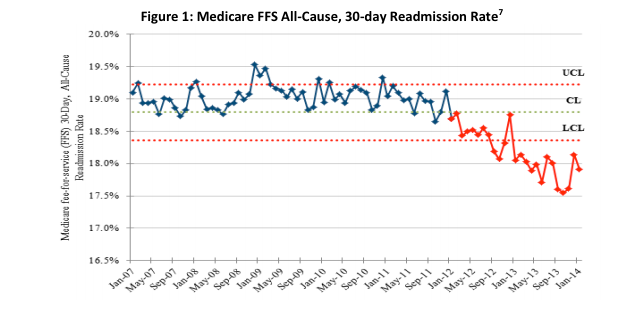

May 14, 2014 — The Department of Health and Human Services (HHS) announced that new preliminary data show an overall 9 percent decrease in hospital-acquired conditions nationally during 2011 and 2012. National reductions in adverse drug events, falls, infections and other forms of hospital-induced harm are estimated to have prevented nearly 15,000 deaths in hospitals, avoided 560,000 patient injuries and approximately $4 billion in health spending over the same period.